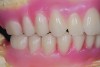

Patient smile shown 3 years post-treatment.

Figure 19

Dental rehabilitation with the All-on-4 treatment concept is often a life-changing event for edentulous and terminal dentition patients that results in unprecedented quality of life improvements (Figure 17 through Figure 20).